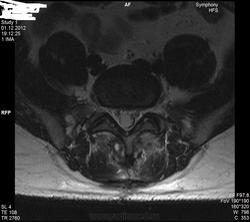

Уважаемые специалисты. МРТ после операции 8 нед.

Операция геминоламинэктомия L4-5 с установкой системы динамической стабилизации между остистыми 4-5.

После операции боли в пояснице прошли, боль в коленях и голенях осталась в неизменном виде. Ниже верхней трети голени боль не опускается.

Левая нога болит больше, но и правая бывает.

По задней стороне туловища в ногах болей никогда не было. Уважаемый специалист, к сожалению не рентгенолог, утверждает что нет никаких признаков радикулопатии. Не посмотрите своим профессиональным взглядом.